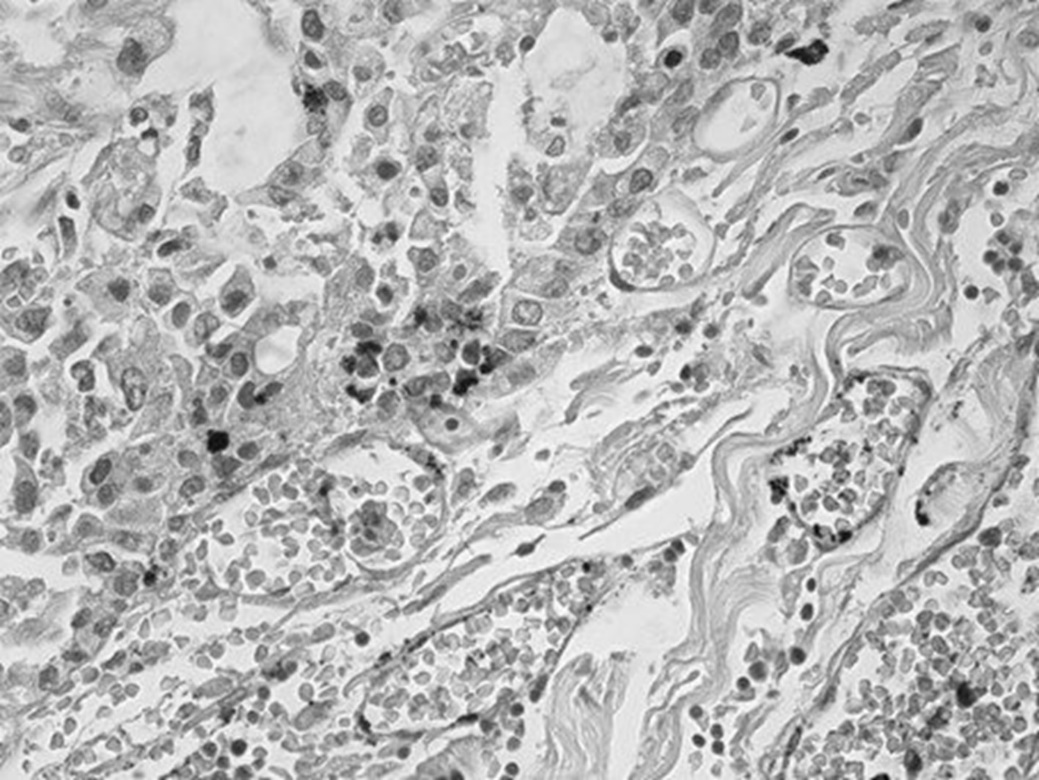

Ниже приводим результат посмертного гистологического исследования ткани печени: «Опухоль представлена полями крупных клеток, не формирующих упорядоченные трабекулярные структуры, с крупными ядрами. Во многих клетках – фигуры митоза, в том числе атипические. Ядра клеток характеризуются выраженным полиморфизмом, многие из них содержат крупные эозинофильные ядрышки. Наряду с атипией и высокой митотической активностью отмечается высокий ядерно-цитоплазматический коэффициент (соотношение площади ядра и цитоплазмы). Клетки располагаются как группами, так и изолированно, разделены узкими прослойками стромы (рис. 2). Опухолевая ткань с обильной васкуляризацией (рис. 3). Во многих сосудах встречаются опухолевые эмболы (рис. 4). Гистологическое заключение: низкодифференцированная гепатоцеллюлярная карцинома (G3), мультифокальный рост опухоли».

Рис. 3. Обилие полнокровных сосудов в прослойках соединительной ткани. Окраска гематоксилином и эозином, ув. 400